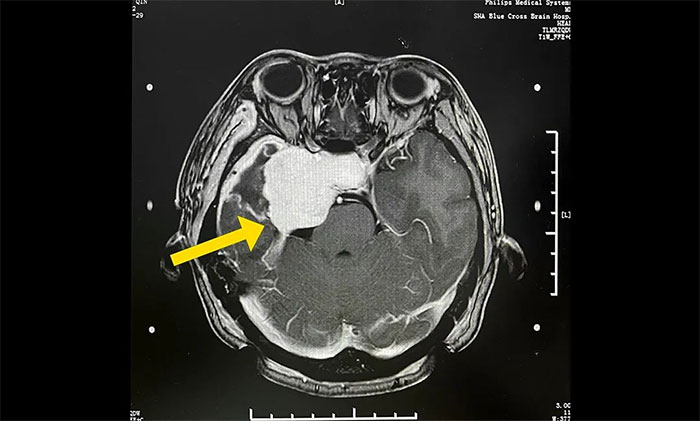

今年初醫(yī)院收治了一位女性患者。該患者因突發(fā)視力模糊,頭暈無法獨(dú)立行走,在外院檢查發(fā)現(xiàn)腦部右側(cè)鞍旁腫塊,手術(shù)病理診斷為海綿狀血管瘤。

▲ 入院時(shí)MRI檢查影像

腫瘤科(放療)頭部伽瑪?shù)督M陳琦主任完善檢查并開展多學(xué)科評估討論,其右側(cè)鞍旁海綿狀血管瘤與視神經(jīng)等重要結(jié)構(gòu)相鄰,若不及時(shí)干預(yù)治療,可因占位壓迫進(jìn)一步加重神經(jīng)功能障礙,甚至導(dǎo)致失明。而該部位病灶的手術(shù)治療難度高、風(fēng)險(xiǎn)大,術(shù)中可能對患者神經(jīng)功能造成嚴(yán)重?fù)p害,應(yīng)考慮采用創(chuàng)傷較小的伽瑪?shù)吨委煛?/p>